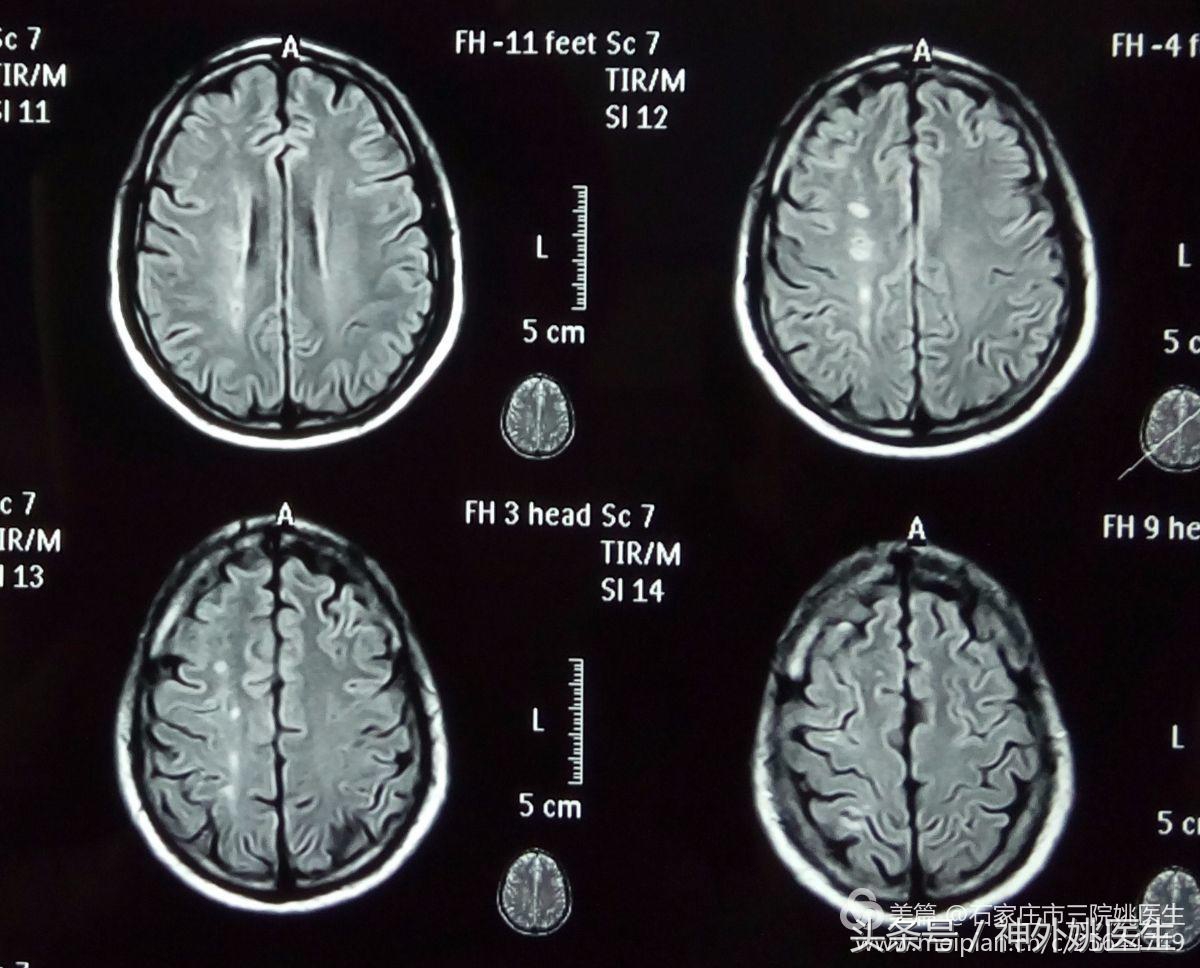

2.头MRI: Flair像示右额顶叶缺血灶(图2)。

图2